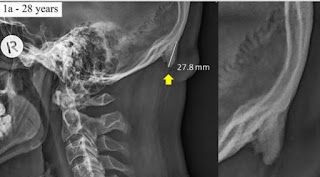

Uma pesquisa de uma dupla de cientistas australianos aponta que jovens que ficam muito tempo com a cabeça dobrada para baixo, em uma posição comum para olhar a tela do celular, podem desenvolver uma protuberância na parte de trás do crânio.

O crescimento é comparável a um calo, e fica na parte de trás, na junção entre o crânio e o pescoço.

Shahar e Sayers afirmam que a prevalência dessa protuberância em jovens adultos aponta para uma mudança na postura das pessoas que foi causada pelo uso de tecnologia.

Smartphones e outros aparelho estão contorcendo a forma humana, de acordo com eles, porque os usuários precisam curvar a cabeça para a frente.